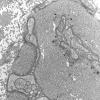

PERIPHERAL NEUROPATHY

4 AXONAL DEGENERATION

3 Electron Microscopy (6)